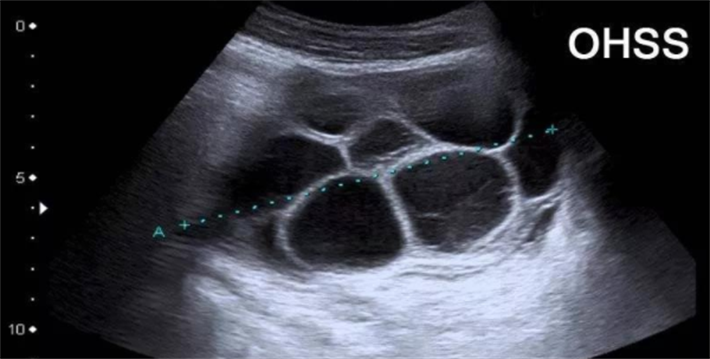

为了获得多个成熟卵子,试管婴儿周期需要使用促排卵药物,其有效成分为卵泡刺激素类似物,能够促使卵巢内多个基础卵泡同步发育。在此过程中,体内雌激素水平会相应升高。在规范的用药方案下,这种升高处于生理可接受范围,通常不会对健康造成损害。然而,若促排卵方案缺乏个体化调整、用药剂量不当或监测不及时,则可能诱发卵巢过度刺激综合征(OHSS)。OHSS表现为腹胀、腹痛、恶心、呕吐,严重者可出现胸腹水、血液浓缩及血栓形成,需要住院干预。